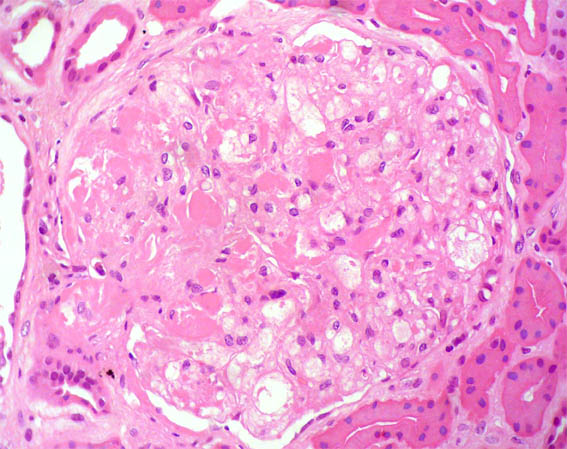

A male patient, 32 years old, was referred for renal biopsy because of a 2 year history of progressive proteinuria until full nephrotic syndrome, without impaired renal function.

Laboratory: normal blood count, creatinine 1.1 mg/dL, BUN 19 mg/dL. Proteinuria 7.3 g/24h with no casts or hematuria. Tests negative for viruses and autoimmunity. Normal complement. Negative cryoglobulins.

See the images of the renal biopsy:

Figure 1. H&E, X100.